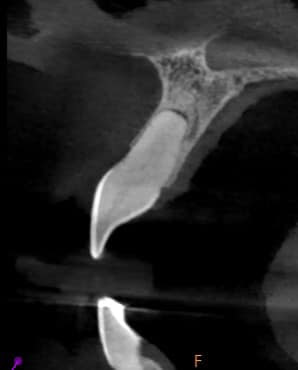

Tooth #11 with a calcified canal following traumatic injury

Tooth #11 with a calcified canal following traumatic injury. The tooth was symptomatic with positive percussion. The referring dentist attempted root canal treatment without success. The patient presented with a CBCT scan.

CBCT showing calcified canal